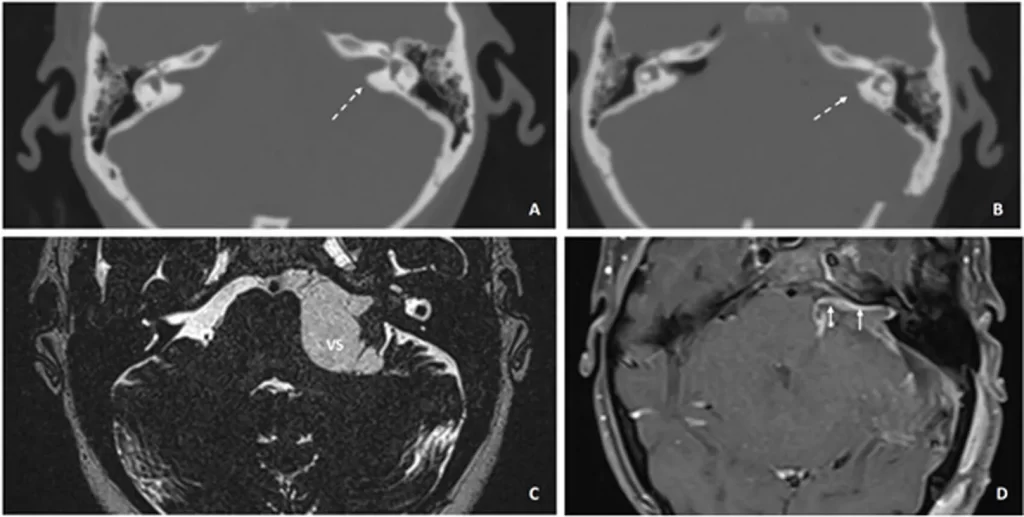

Figura 2: Tomografía computarizada (TC) preoperatoria de los huesos temporales:

A) de un paciente con un SV izquierdo de gran tamaño;B) la imagen postoperatoria muestra el área del hueso del CAI que ha sido removido, resaltada con flechas discontinuas.C) La resonancia magnética (RM) ponderada en T2 en estado estacionario muestra el gran SV antes de la operación;D) imagen postoperatoria (día tres) en RM ponderada en T1 con gadolinio. Las flechas cortas destacan el realce postoperatorio a lo largo de todo el trayecto del nervio facial.Contexto clínico: